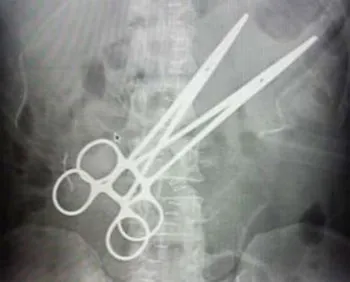

mala praxis